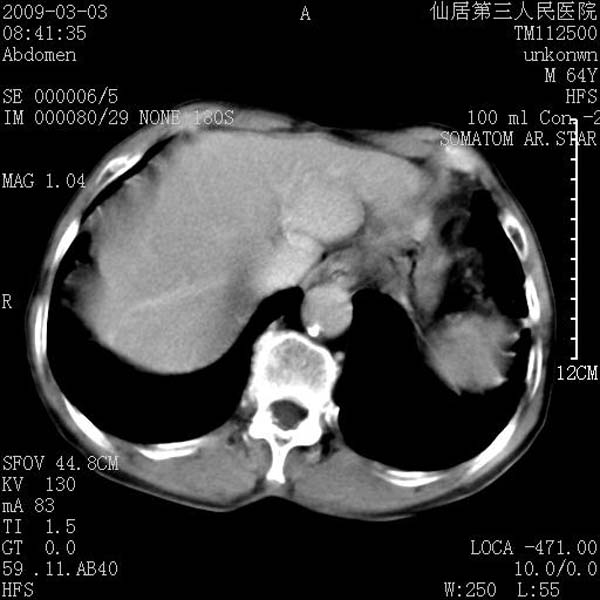

标题: CT18469:男性,64y,体检B超示肝脏低回声肿块,有胃溃疡手术 [打印本页]

标题: CT18469:男性,64y,体检B超示肝脏低回声肿块,有胃溃疡手术

患者,男性,64y,体检b超示肝脏低回声肿块,有胃溃疡手术史。

从平扫及增强的特点来看,支持肝脏腺瘤并出血。

支持肝脏腺瘤并出血。期待结果。

ct值呢?感觉没强化,象囊性。

考虑肝囊肿并出血可能性大.

支持肝脏腺瘤并出血。期待结果

考虑高密度囊肿可能性大

考虑高密度囊肿可能性大支持